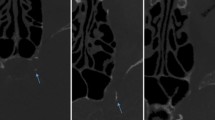

a and b Maximum intensity display CTA coronal view (a) and sagittal view of the left side (b) demonstrates the carotid bifurcation calcium bilaterally (yellow arrows). There is also a small amount of calcified plaque more cephalad in the right internal carotid artery (red arrows). Decent quality CT angiographic images such as these were obtainable from the multidetector neck CT raw data. Note that the carotid calcifications are easily distinguishable from the arterial lumen due to the higher Hounsfield unit range of calcium. c (right and left carotids) Prior to carotid calcium measurement, the 3D data set was sculpted to a subvolume to exclude bony calcium related to spine, thyroid, and hyoid cartilage. d A density threshold was then visually adjusted (within a range of window 10–20 HU and level 250–500 HU) to include only calcium within the volume (thus excluding luminal contrast enhancement). Volume measurements were then calculated with an automated feature of the software. This patient has a left carotid calcium volume of 0.13 cc, and a right calcium volume of 0.10 cc. Note the small amount of calcium more cepahalad in the right ICA (red arrow). e Measurements of stenotic right and left ICA luminal diameter. CTA stenosis measurements were obtained in a NASCET-like fashion by measurement of ICA luminal diameter at the point of maximum stenosis (same patient as a–d). Non-calcified plaque (yellow arrow) was distinguishable from calcified plaque in this patient. f Measurements of the normal right and left ICA luminal diameter. At a level 2 cm or greater cephalad to the maximal stenosis, the more normal ICA diameter is obtained. This patient had an approximately 45% stenosis on the right, and 43% on the left

After excluding extraneous cause of carotid involvement (such as tumor encasement/invasion), bifurcation vascular anatomy was evaluated by manipulating window/level (window 900–1200 HU, level 300–500 HU) to view calcified and non-calcified plaque and measure internal carotid stenoses. Calcified plaque was easily distinguished from non-calcified plaque by manually and visually manipulating window/level. The single reader was not blinded to results of calcium volume determination before measuring degree of stenosis. All measurements of stenosis were obtained on 1 mm thickness images to minimize volume averaging. To avoid overestimation of luminal diameter, the images used to measure luminal diameter stenosis were always obtained from an image plane perpendicular (90°) to the axis of the vessel. This often required reorientation of the image plane. Vascular luminal contrast enhancement was easily separated visually from calcified plaque (if present) by manual manipulation of window/level settings. This manipulation was monitored closely to avoid accidental inclusion of vascular enhancement in the calcium volume. To evaluate for the presence of stenosis, the observer measured the cross-sectional luminal diameter in millimeters at the narrowest location (Fig. 1e) (even in the absence of significant plaque) and measured the more normal/non-stenotic internal carotid artery diameter at least 2 cm above the site of narrowing/plaque (Fig. 1f). Thus, an attempt was made to adhere to North American Symptomatic Carotid Endarterectomy Trial (NASCET) criteria as closely as possible [14] when performing stenosis measurements. Locations of narrowing in the ICA were evaluated at any level from the carotid bifurcation to the skull base; common carotid artery narrowing and intracranial ICA narrowing were not evaluated in this study. Images of the final calcium burden volume and measurements of luminal diameter were stored for future reference. A single observer initially evaluated all studies, although a second observer re-evaluated those patients with “significant” stenoses.